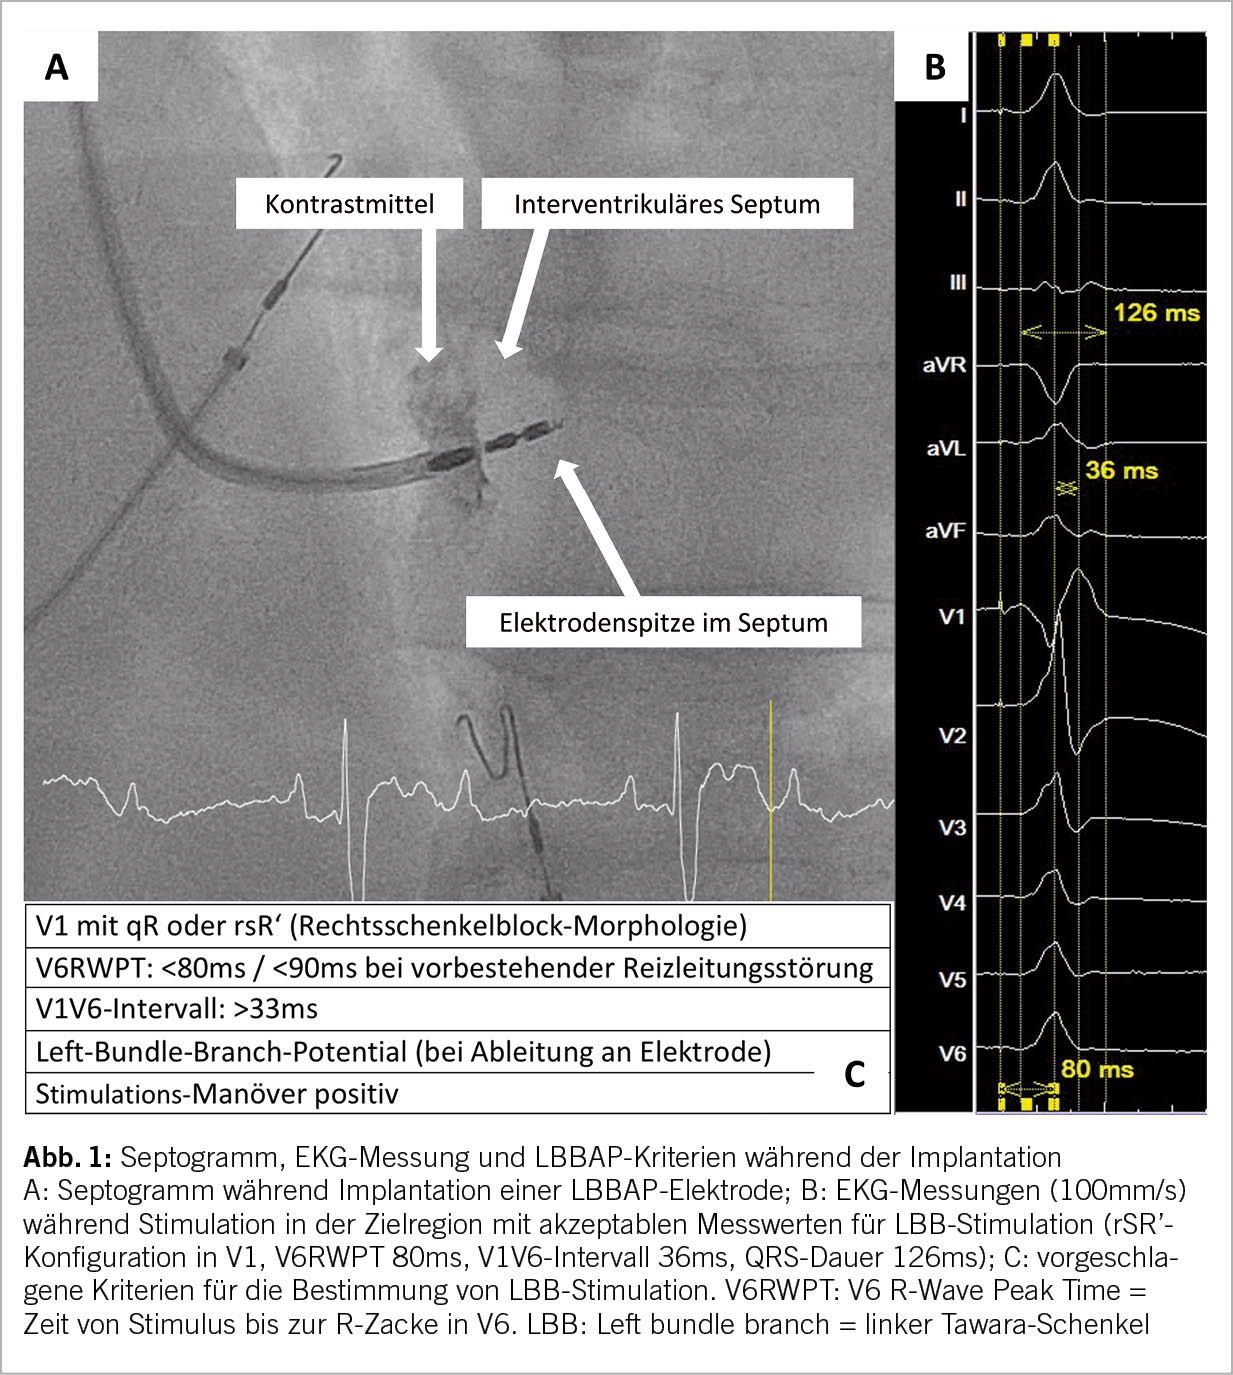

Die Patientenvorbereitung vor einer LBBAP-Implantation ist analog einer klassischen Schrittmacherimplantation. Neben einer standardmässigen Blutuntersuchung (Infektparameter, Elektrolyte, Nierenfunktion) wird eine präoperative Echokardiographie zur Evaluation der linksventrikulären systolischen Funktion, Septumdicke, Dimensionen der Herzhöhlen sowie möglicher Klappenpathologien empfohlen. Während der Implantation erfolgt zusätzlich die kontinuierliche Ableitung eines 12-Kanal-EKGs mit schneller Laufgeschwindigkeit (meist 100mm/s) zwecks Dokumentation der Stimulationsmorphologie während der LBBAP-Implantation. Falls die Implantation in einem Elektrophysiologie-Labor durchgeführt wird, kann ergänzend neben dem 12-Kanal-EKG fortlaufend das endokardiale Signal von der Spitze der Elektrode im Herzen dargestellt werden. Zur Implantation können verschiedene Elektroden mit oder ohne innere Lumen sowie dazugehörige lange Schleusen verwendet werden (9, 10). Die anschliessende LBBAP-Implantationstechnik hat sich seit der Erstbeschreibung 2017 nicht wesentlich verändert (6, 11). Nach der venösen Punktion erfolgt die Platzierung der Elektrode über eine lange Schleuse am basalen rechtsventrikulären interventrikulären Septum. Die Lokalisation der idealen Position erfolgt anhand anatomischer und elektrokardiographischer Kriterien mittels Pacemapping (11). Das anschliessende Einschrauben der Elektrode in das interventrikuläre Septum hinein erfolgt durch Drehen der gesamten Elektrode und unter Monitorisierung des Elektrogramms, der unipolaren Impedanz, der radiologischen Dokumentation sowie des Oberflächen-EKGs während der unipolaren Stimulation (11, 12). Die Drehbewegungen sollten gestoppt werden, wenn die typische LBBAP-Stimulationsmorphologie erreicht wurde (Abb. 1) oder ventrikuläre Extrasystolen mit LBBAP-Morphologie während dem Einschrauben provoziert werden (sogenannte «template beats» oder «fixation beats») (13-15). Ein plötzlicher Abfall der unipolaren Stimulationsimpedanz >200 Ohm, anhaltende unipolare Stimulationsimpedanzen < 400 Ohm, polymorphe VES mit Rechtsschenkelblock-Morphologie oder ein reduziertes Sensing sind Hinweise für eine mögliche Perforation in den linken Ventrikel.

Bezüglich der elektrophysiologischen Kriterien für eine erfolgreiche Stimulation des linksseitigen Tawara-Schenkels (LBB) herrscht derzeit kein wissenschaftlicher Konsens. Diese sind derzeit noch Gegenstand der aktuellen Forschung und wurden noch nicht in grossen prospektiven Studien validiert (16). Trotzdem haben sich in der aktuellen Literatur folgende Kriterien zunehmend konsolidiert: Bei Betrachtung des stimulierten Oberflächen-EKGs sollte bei Erreichen von LBBAP eine rechtsschenkelblockartige QRS-Morphologie (qR oder rsR‘ in V1) auftreten (Abb. 1). Die Zeit bis zur Aktivierung des linken Ventrikels (V6RWPT: Zeit bis zur R-Zacke in V6) sollte bei hohem und tiefem Output stabil kurz (<70-90ms) und idealerweise nicht länger als intrinsisch gemessen sein, als Zeichen der Stimulation des LBB (11, 15, 17). Das V6-V1-Interpeak-Intervall widerspiegelt die Zeit zwischen der Aktivierung des linken und des rechten Ventrikels und ist bei einem V6-V1 Intervall >33ms ein weiteres diagnostisches Kriterium für LBB-Stimulation (18). Manchmal lässt sich auf dem von der Elektrodenspitze abgeleiteten Elektrogramm ein scharfes hochfrequentes Linksschenkelpotential 20 – 35ms vor dem lokalen ventrikulären Elektrogramm nachweisen (19). Zuletzt existieren verschiedene aufwändigere Stimulations-Manöver (Nachweis von nicht-selektiver und selektiver LBB-Stimulation) (20). Wenn eine zufriedenstellende Position der Elektrode erreicht wurde, kann ergänzend ein Septogramm zur Darstellung der Tiefe der Elektrode im interventrikulären Septum erfolgen mittels Kontrastmittel-Applikation über die lange Schleuse (Abb. 1).